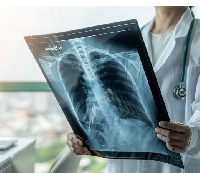

Любого доктора можно быстро подготовить как рентгенлаборанта и дать необходимые знания для оценки рентгенограмм.

Изучение проблемы низкого качества рентгенограмм на Вашем оборудовании.